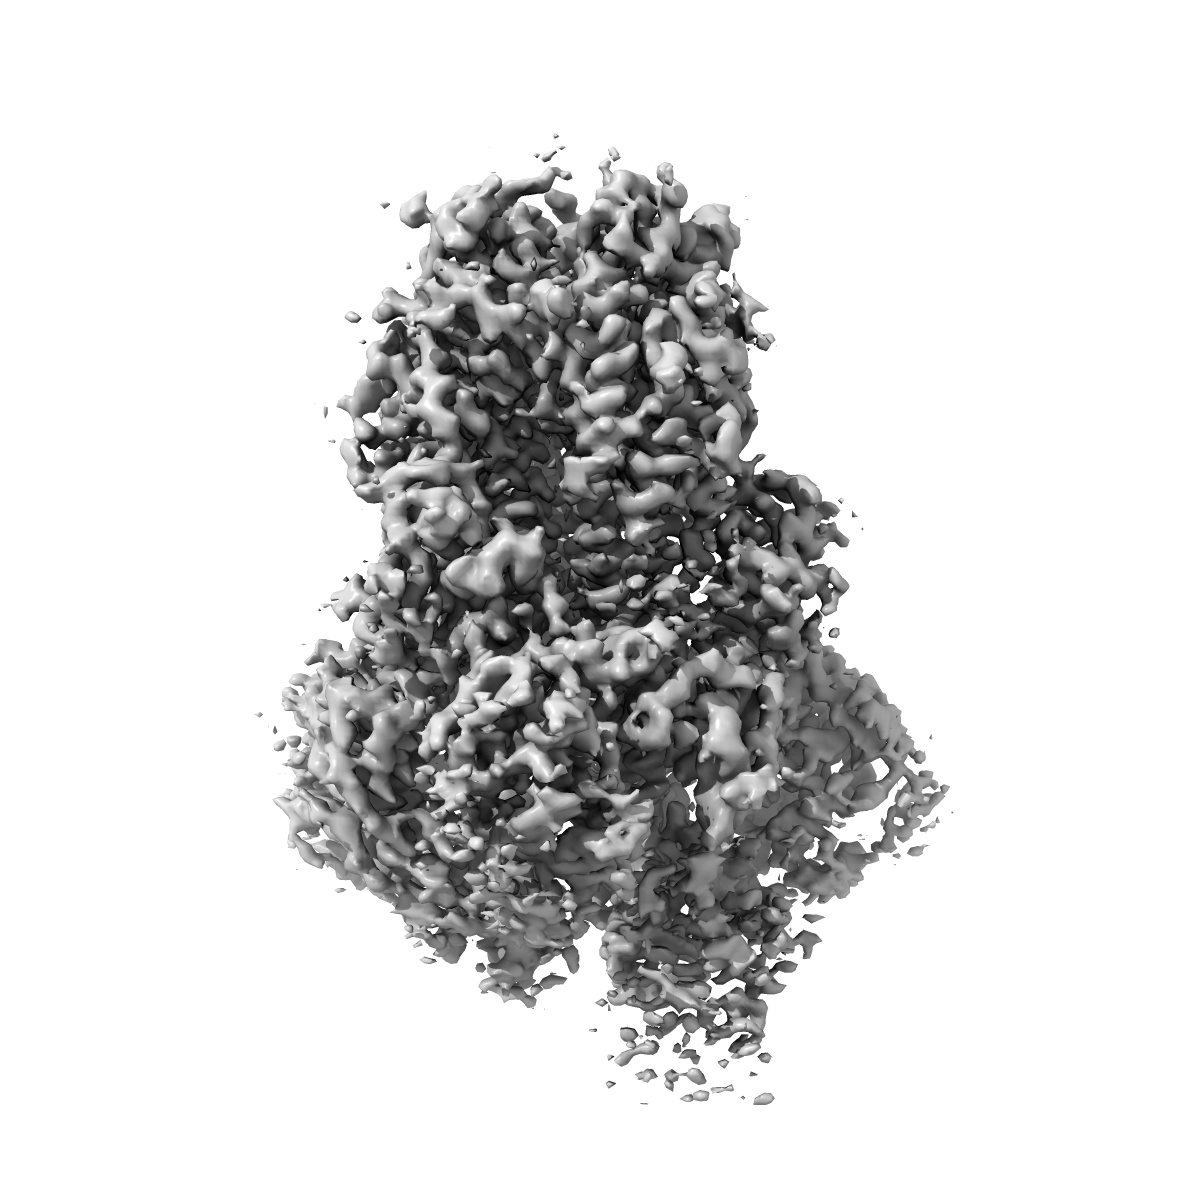

SARS-CoV-2 BA.2.75 S Trimer (1 RBD Up)

Single-particle3.45 Å

Sample: BA.2.75 Spike trimer

Characterization of the enhanced infectivity and antibody evasion of Omicron BA.2.75.